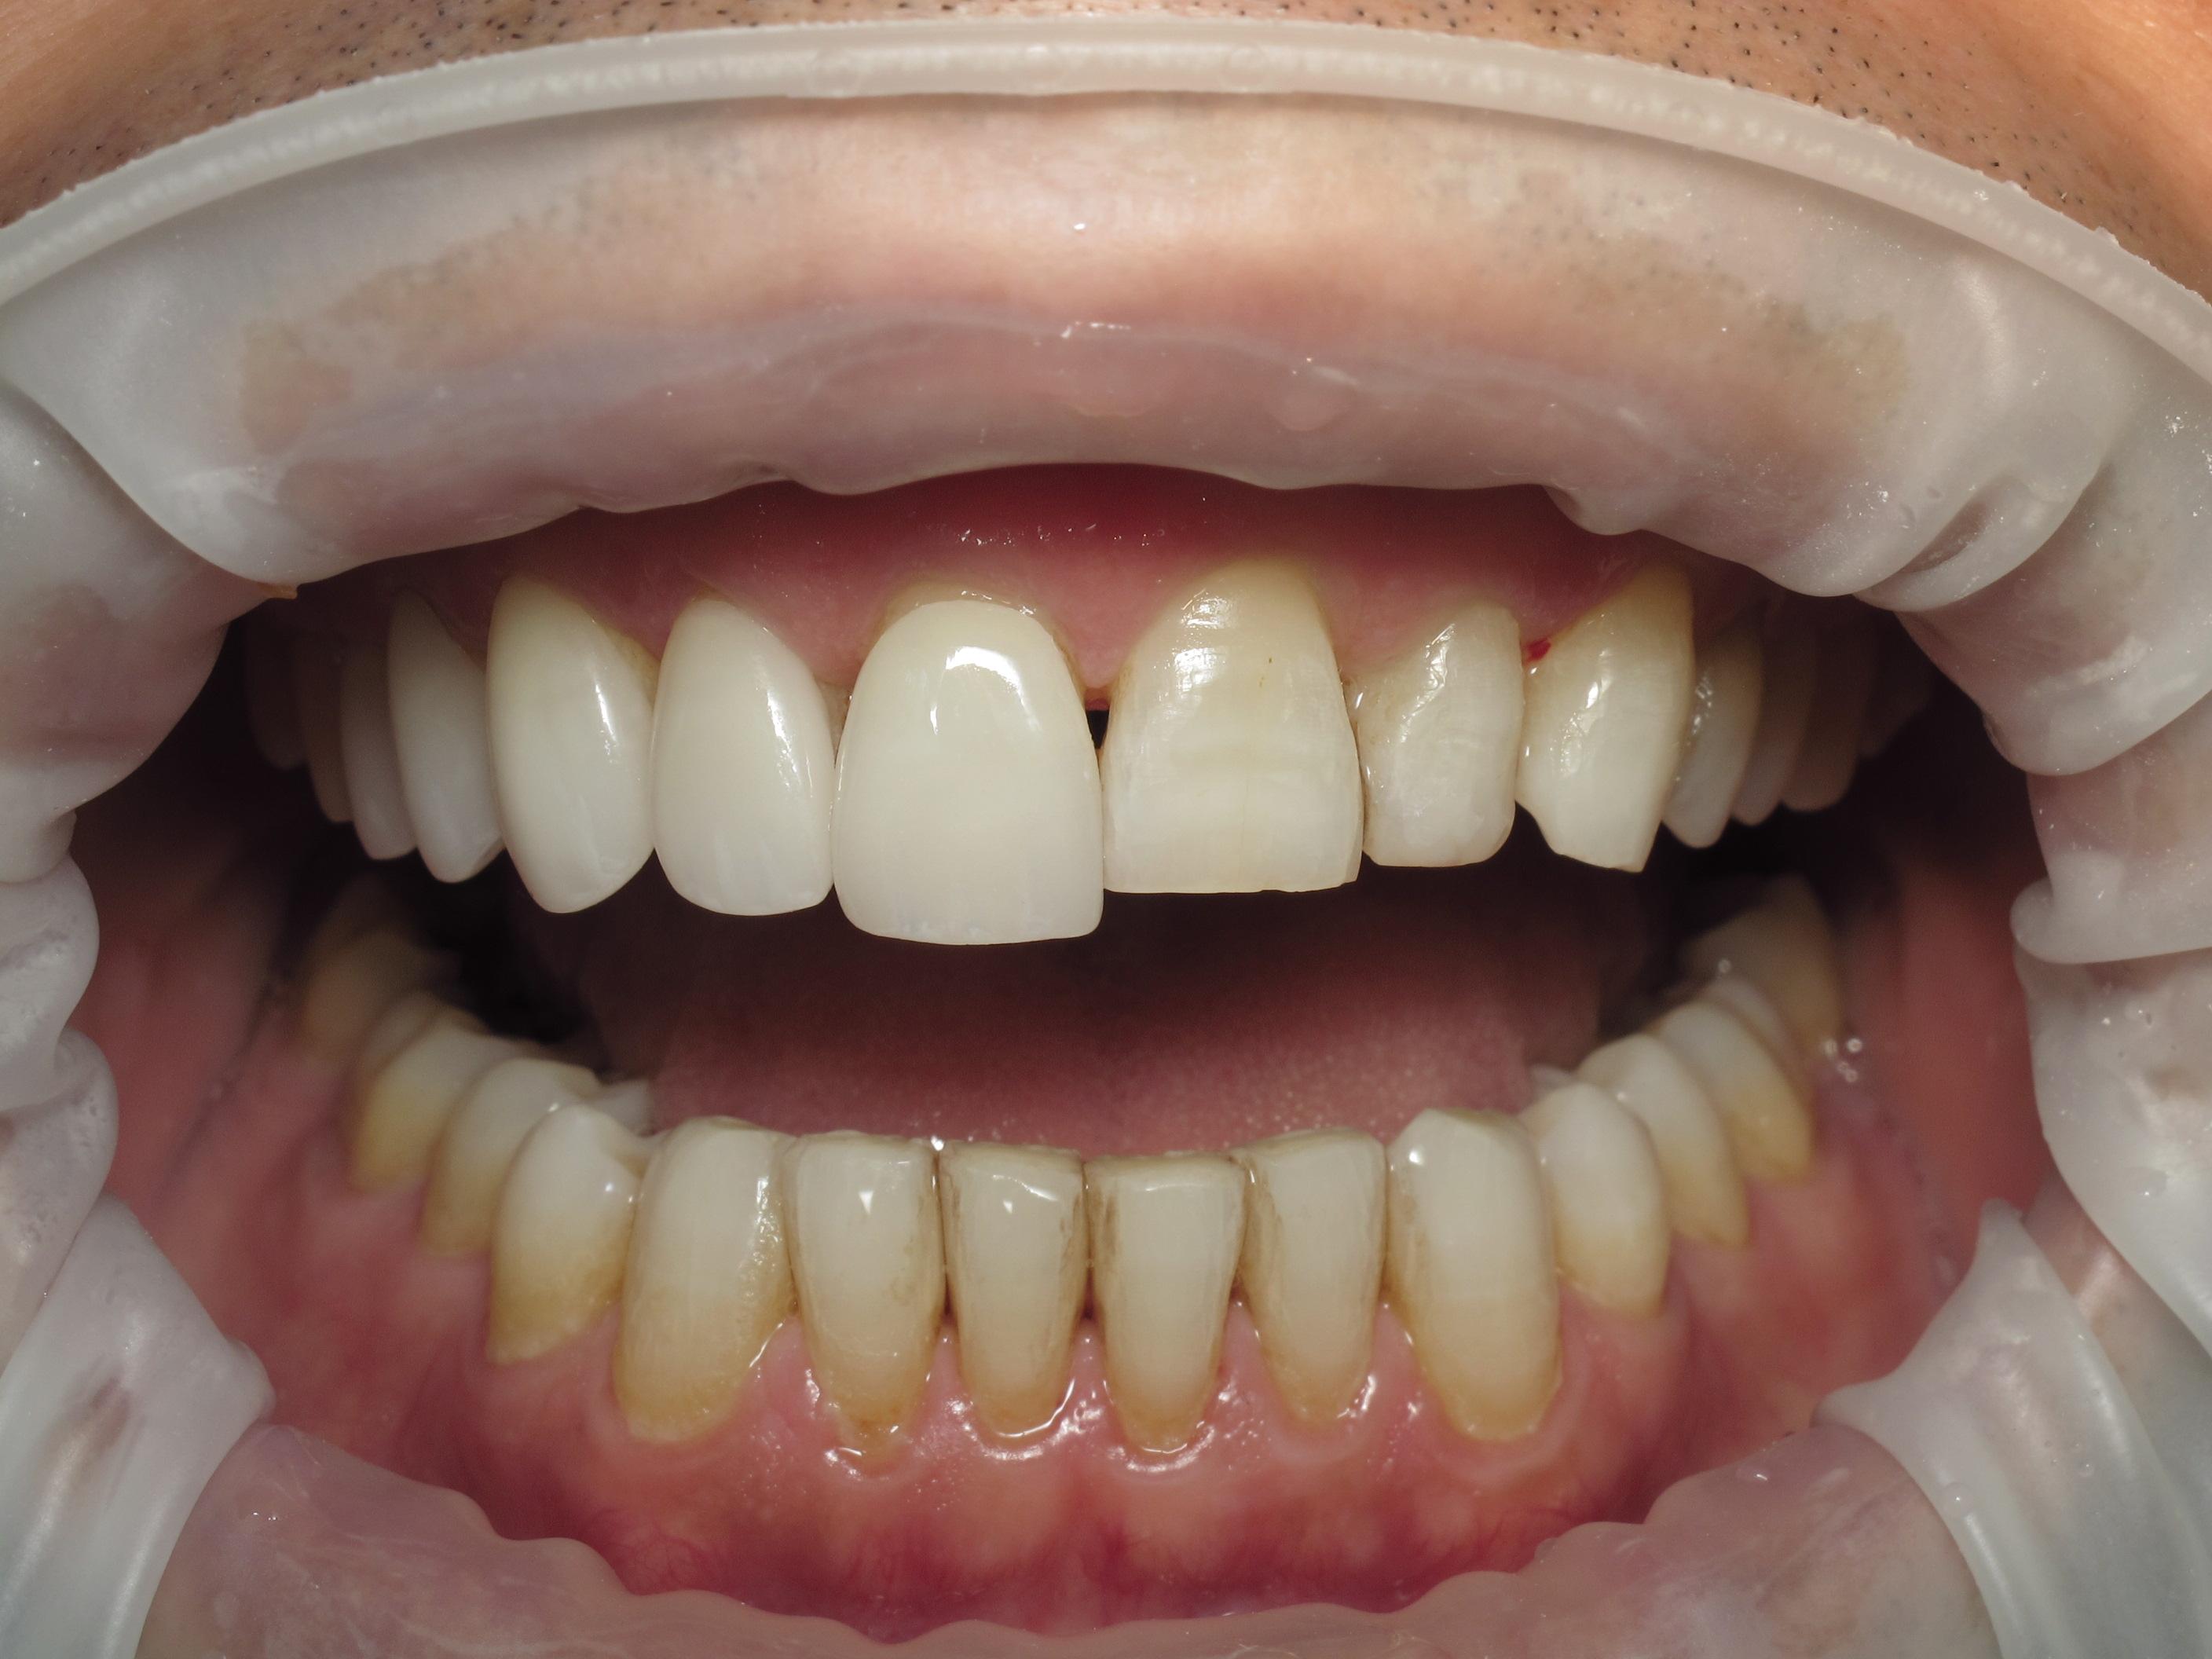

https://demo.discussdentistry.com/forums/topic/no-prep-veneers/#post-26022 <![CDATA[No prep veneers]]> https://demo.discussdentistry.com/forums/topic/no-prep-veneers/#post-26022 Mon, 15 Apr 2024 03:43:21 +0000 Amit Kumar The patient is a successful physician who desired an improved smile but did not want to “shave down” his teeth.

No prep veneers were delivered from the upper second bi-cuspid to the second bi-cuspid on the contra-lateral side.  No temporaries were needed.

The patient also wanted to include his lower anterior teeth, however,Pre opPre op right sidePre op left sideTry in right sideTry in left sideFinal 1Final 2 there was not enough clearance to accomplish this using no-prep technique.

You can note that the upper central was lengthened by 20%.